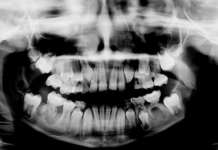

Materiali e metodi. Sono state estratte polpe dentali da soggetti adulti in salute con età dai 16 anni agli over 66 anni. Sono state isolate e coltivate cellule staminali adulte in presenza di terreni differenziativi. È stata indagata la capacità proliferativa delle cellule staminali per ciascun gruppo d’età, attraverso il calcolo del time doubling e analisi immunoistochimiche per specifici marcatori.

Sono state estratte 120 polpe dentali da terzi molari di persone adulte sane dell’età compresa tra 16 anni e over 67 anni (20 denti per ciascuno dei seguenti gruppi di donatori: 16-25, 26-35; 36-45; 46-55; 56-66; over 67).

Prima dell’estrazione, è stata fatta l’anamnesi medica e odontoiatrica a ciascun soggetto. Solamente le persone prive di patologie sono state selezionate per l’analisi della polpa. Ciascun paziente si è sottoposto per una settimana a igiene dentale professionale. Prima dell’estrazione, la corona del dente è stata ricoperta per 2 minuti con gel a base di clorexidina al 0.3% (Forhans, New York, NY).

Sono stati utilizzati per questo lavoro solamente i denti per i quali non era stato necessario eseguire l’odontotomia durante le manovre chirurgiche.

Una volta avulsi, i denti sono stati fratturati meccanicamente. In ambiente sterile, con una fresa a pallina montata su turbina, è stato eseguito un solco circumferenziale a livello della giunzione amelocementizia, immergendo lo strumentario e il dente all’interno di una contenitore reniforme con acqua fisiologica sterile. La refrigerazione ha permesso di evitare il surriscaldamento della polpa e la conseguente necrosi cellulare. Con delle pinze sono stati poi separati i due frammenti dentali, con esposizione della polpa, la quale è stata rimossa con degli escavatori dentinali o delle curette di Gracey.